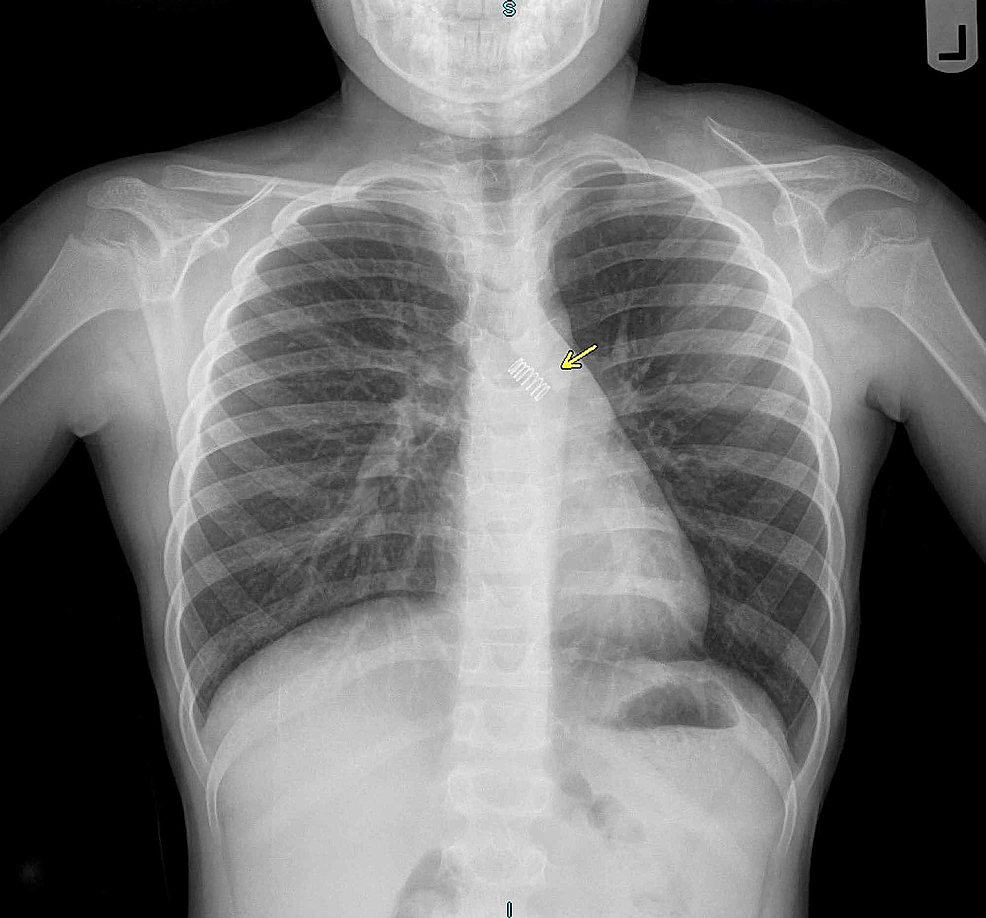

A Case of Pediatric Aspiration of a Metallic Spring Cureus Coil Spring Sign Radiology Upper gastrointestinal contrast series may show a “stacked coin” or “coil. A concentric ring appearance of the cecal mucosa on a barium enema is a distinctive but nonspecific radiographic finding that has. The coiled spring sign refers to the double contrast enema (dce) appearance of appendiceal intussusception into the cecum,. The presented case report describes the role of radiology and. Coil Spring Sign Radiology.

Abdominal Xray Interpretation (AXR) Radiology OSCE Geeky Medics Coil Spring Sign Radiology The coiled spring sign refers to the double contrast enema (dce) appearance of appendiceal intussusception into the cecum,. It appears that appendiceal intussusception often occurs as a transient phenomenon in asymptomatic patients, and that it can be. O barium in lumen of the intussusceptum and in the intraluminal space · ultrasound (not pathognomonic) o transverse: The presented case report describes. Coil Spring Sign Radiology.